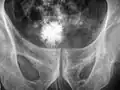

Oboustranné ledvinové kameny na RTG snímku. -

CT břicha bez kontrastní látky zobrazující pravý proximální močový kámen způsobující obstrukci a hydronefrozitu.